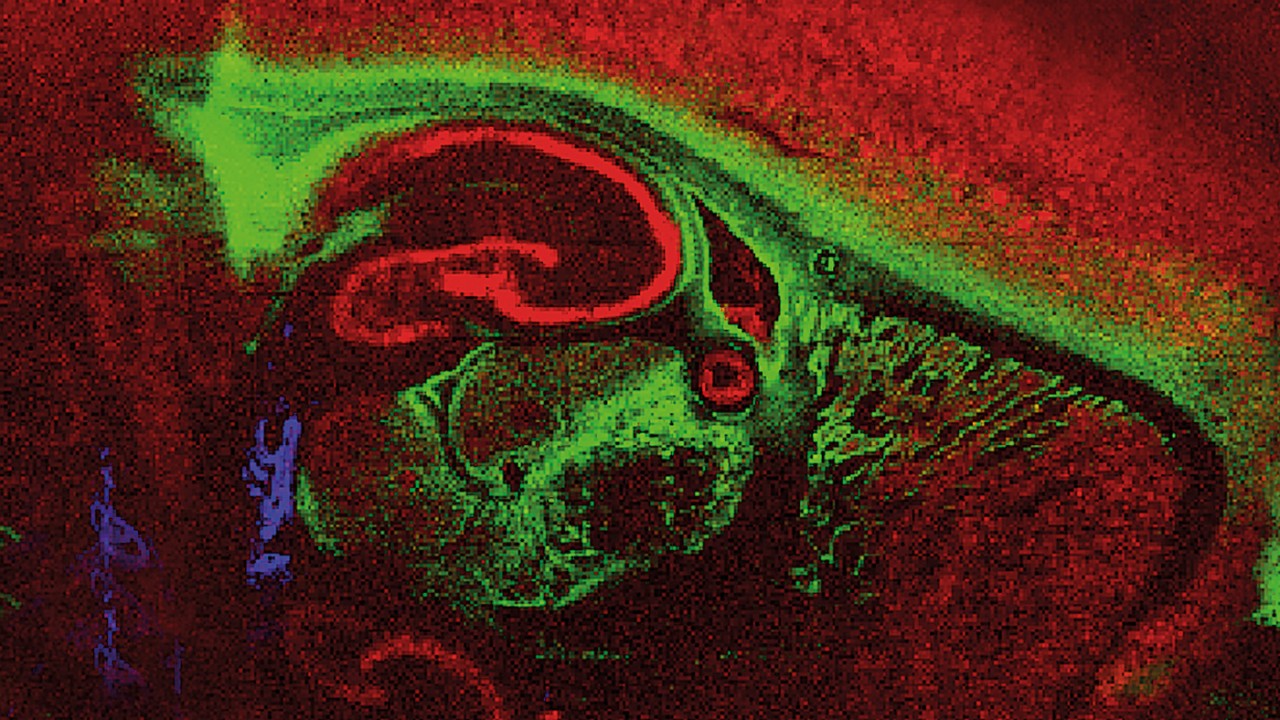

Bruker´s MALDI Imaging solutions - Gain Deeper Insights

Since the discovery of MALDI in the mid 80's this fast and high-throughput enabling ionization made its way into a variety of applications. The inherent speed of MALDI-TOF analysis from sample to result allows for fast answers to your analytical questions. The laser aiming at different positions gives rise to spatial, molecular information as used e.g. for MALDI Imaging for tissues.